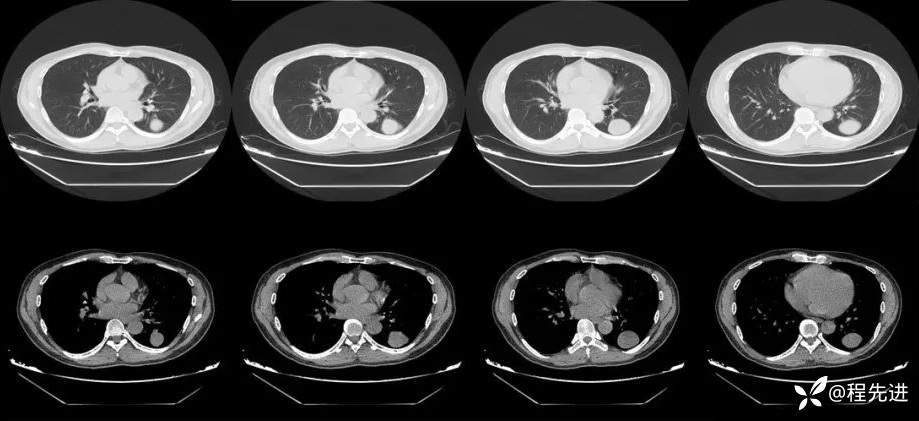

CT平扫: